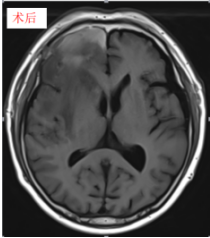

神经外科接诊患者后,经头颅CT检查提示右额叶占位性病变,肿瘤对周围脑组织压迫显著,病情危急。突如其来的病情让患者及家属深受打击,情绪焦虑不安。神经外科第一时间将患者收治入院,完善相关检查、全面评估病情,明确诊断并制定周密的手术治疗方案,力争尽早解除患者颅内压迫,防止病情进一步恶化。住院期间,患者颅内占位压迫效应持续加重,症状进展明显,手术指征明确、刻不容缓。为最大限度保障患者生命安全,避免患者在节日期间病情加重、延误救治,丁小明将手术安排在春节前最后一个工作日进行。

手术过程中,团队凭借扎实的专业功底、娴熟的显微操作技术及严谨细致的诊疗作风,精准分离、精细操作,在完整切除病变组织的同时,最大限度保护正常脑组织及神经功能,手术顺利完成。

术后患者生命体征平稳,无新发神经功能不适,恢复情况良好,各项指标逐步改善,为后续治疗奠定了坚实基础。患者及家属对神经外科团队及时、高效、优质的救治深表感激,对丁小明及全体医护人员节日期间坚守岗位、无私奉献的精神深表敬意与感谢。